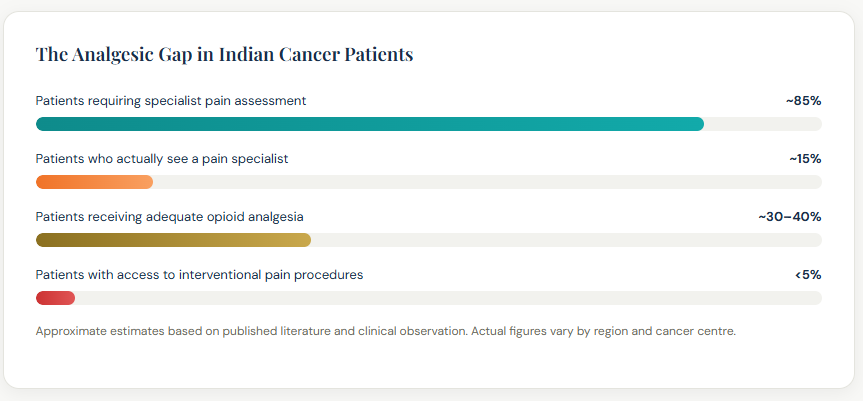

India’s cancer pain crisis is a story of multiple compounding failures of awareness, of access, of stigma, and of a healthcare system where pain specialists are bypassed in the rush from oncologist to hospital, and back again. Consider this: India accounts for nearly 8% of global cancer deaths, yet consumes less than 1% of the world’s medical morphine. That gap is not a reflection of less pain it is a reflection of how catastrophically undertreated that pain is.

In India, the typical cancer patient’s journey looks like this: diagnosis at a government hospital or private oncology centre → chemotherapy or radiation → oncologist follow-up. At no point in this pathway is a pain specialist routinely consulted even when the patient’s pain is severe, or when opioid side effects have become intolerable.

India consumes less than 1% of the world’s medical morphine despite bearing nearly 8% of global cancer deaths. The reasons are multiple: cultural fear of opioids and belief that morphine signals “the end”; regulatory barriers to prescribing; patients bypassing pain specialists and remaining under oncology follow-up alone; lack of specialist pain services outside major cities; and insufficient awareness both among patients and healthcare providers that effective interventional alternatives exist. IBAP Clinics exists to change this for patients in Hyderabad and beyond.